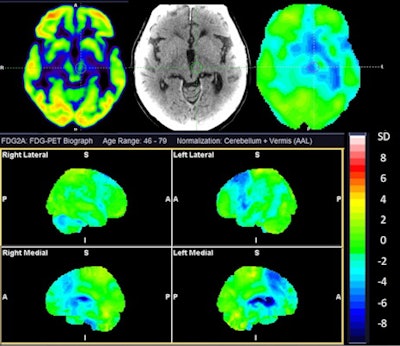

A team led by Naba Jawad Houssein, of Copenhagen University Hospital Bispebjerg in Copenhagen, Denmark, demonstrated that cerebral F-18 FDG-PET scans helped differentiate between subtypes of atypical parkinsonism with significant sensitivity (> 80%) and specificity (> 90%). The results support the use of PET for the clinical diagnosis of atypical parkinsonism, the group noted.

While the diagnosis of atypical parkinsonism is based on clinical criteria, the researchers hypothesized that F-18 FDG-PET scans could provide more detailed data to separate the disorders based on uptake of FDG radiotracer in affected brain regions. Moreover, only a few studies have evaluated the sensitivity and specificity of the technique for this use, the researchers added.

The group identified 156 patients referred for a brain F-18 FDG PET scans between 2017 and 2019 for suspicion of atypical parkinsonism, with imaging analyzed by a nuclear medicine specialist with more than 10 years of experience in PET neuroimaging. The reference standard for comparison was each patient's follow-up clinical diagnosis.